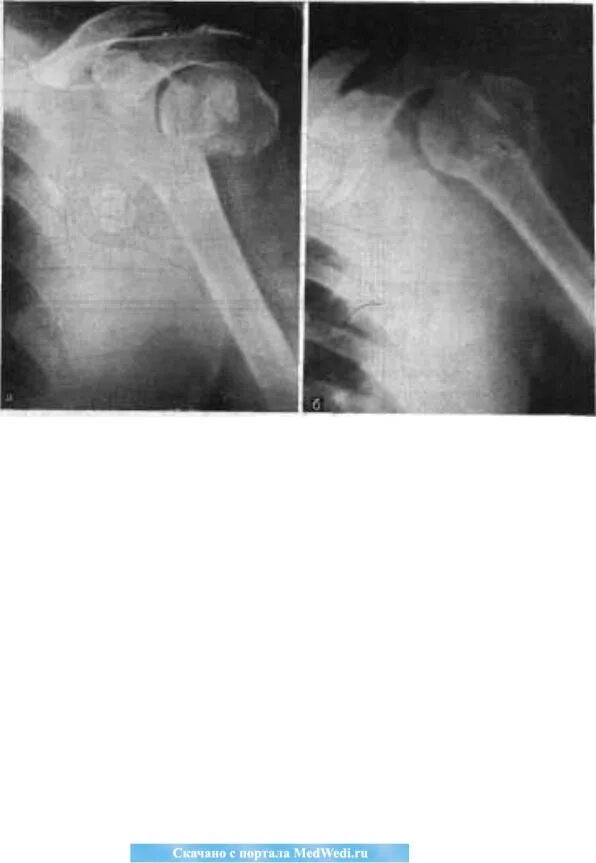

Перелом шейки плеча у пожилых